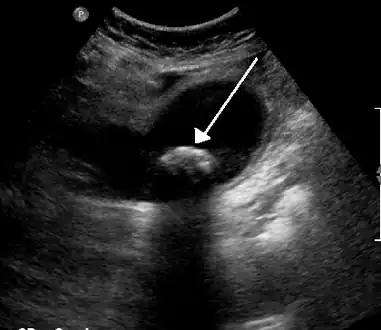

On abdominal ultrasound, sinking gallstones usually have posterior acoustic shadowing. In floating gallstones, reverberation echoes (or comet-tail artifact) is seen instead in a clinical condition called adenomyomatosis. Another sign is wall-echo-shadow (WES) triad (or double-arc shadow) which is also characteristic of gallstones.[43]

-

A 1.9 cm gallstone impacted in the neck of the gallbladder and leading to cholecystitis as seen on ultrasound. There is 4 mm gall bladder wall thickening.